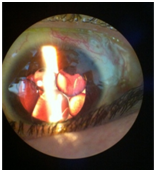

This is a case of 24 years old boy who presented to us due to rapidly progressive deterioration of vision in both eyes over a period of 3 months. His past medical history included a diagnosis of Tourette syndrome (TS) and depression since the age of 14 years. He was not compliant to his medical therapy for fast 1 year. His mother noticed that he was confined to his room for past few days and was stumbling upon the objects at home. She described his motor tics as having blepharospasm, clapping, gouging his fingers into his eyes, and punching himself in the periorbital area. She decided to seek ophthalmologist opinion when she noticed exacerbation in the tic frequency and severe periorbital ecchymosis over the right eye. During the examination, patient was well oriented, did not show any vocal or motor tics and no signs of cognitive impairment. On ocular examination, there was periorbital ecchymosis in the right eye and multiple mechanical scratch marks in the periorbital region laterally and also on face (Figure 1). The nature of the external injuries was commensurate with a tendency of motor tics described by his mother. Ocular movements were full and free. Visual acuity was no perception of light in the right eye and hand movement close to face in the left eye. Slit lamp biomicroscopy showed clear cornea in both eyes (Figure 2). Right eye examination revealed posterior synechiae with near total cataract. There was evidence of KPs, mild aqueous cell and posterior sub capsular cataract in the left eye. Even though the fundus visibility was limited by vitreous hemorrhage, a total retinal detachment with proliferative vitreoretinopathy could be seen in his both eyes (Figure 3). Echography revealed a closed funnel retinal detachment in both eyes (Figure 4).

Figure 1 Periorbital ecchymosis in the right eye.